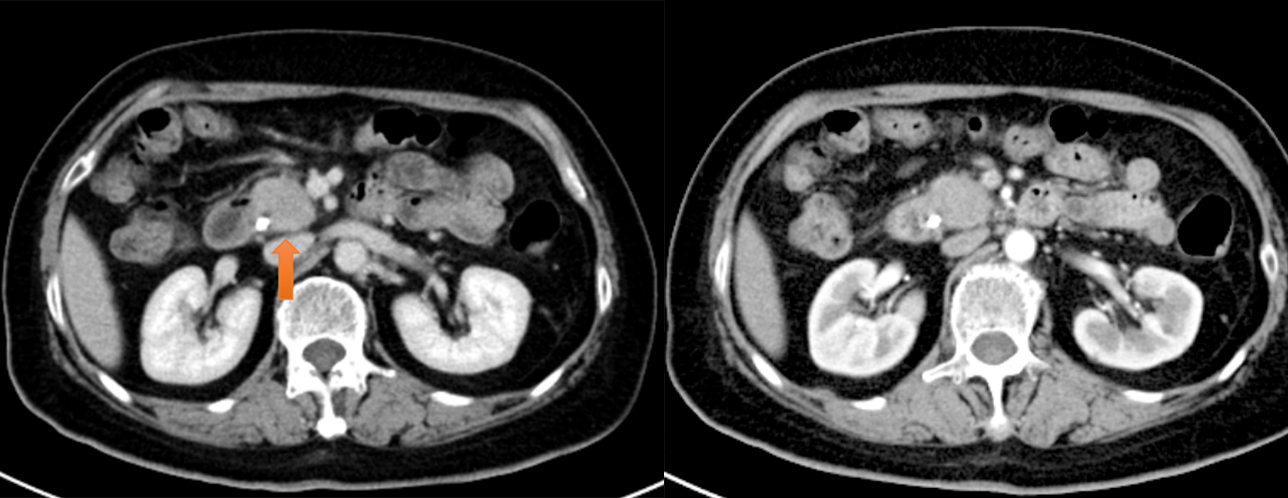

消融术结束前行即刻增强CT扫描:

肿瘤病灶呈低密度改变,无强化,病灶周围血管清晰可见,无出血、消化道穿孔等并发症。

消融术后即刻增强CT影像:

消融区病灶呈低密度及气化改变,未见出血等并发症,消融效果良好。